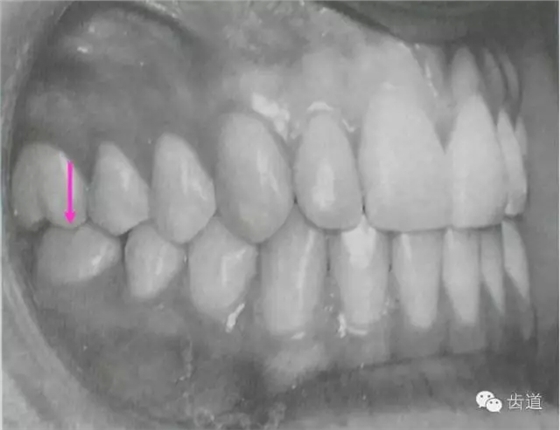

2)上、下頜牙牙冠略向近中傾斜。咬合時(shí)牙的遠(yuǎn)中受力大于近中,這種咬合力對牙體有推向前(向近中)的作用,因而正常時(shí)牙齒基本上是向近中傾斜的。

牙列的完整,牙列中各牙之間的相互支持,在維持咬合的前后向平衡方面,具有重要意義。如果牙齒缺失。位與缺牙遠(yuǎn)中的鄰牙因近中支持喪失,在向前的推動力作用下將向近中移動或傾斜,而位于缺牙近中的鄰牙也會因缺少遠(yuǎn)中支持,在向后方向的動力作用下向遠(yuǎn)中移動或傾斜。